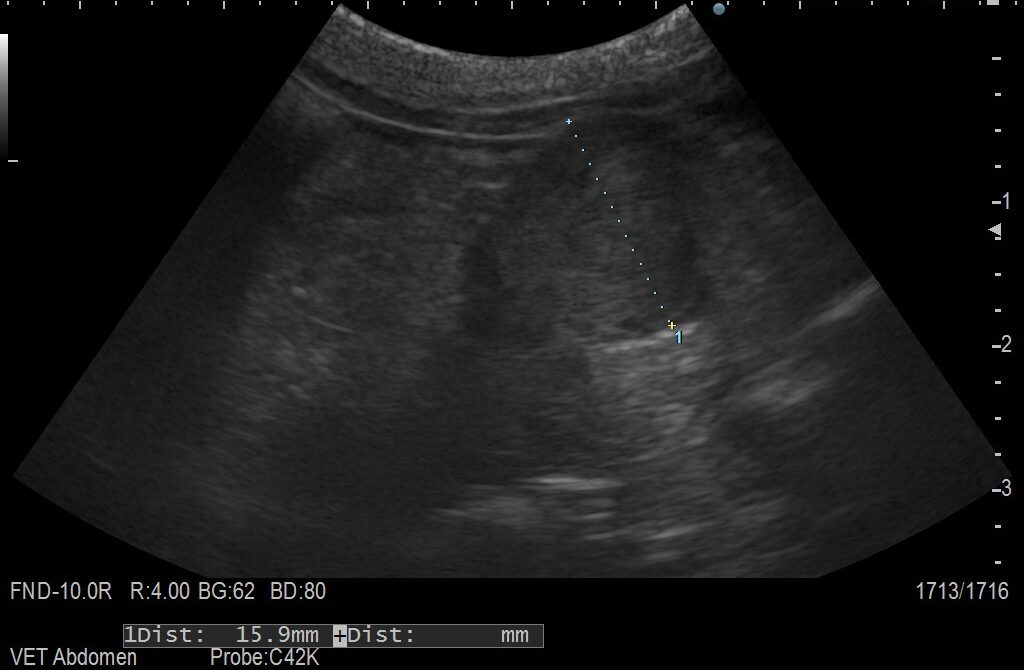

エコー写真① エコー写真②

超音波検査で見つかった子宮腫瘍